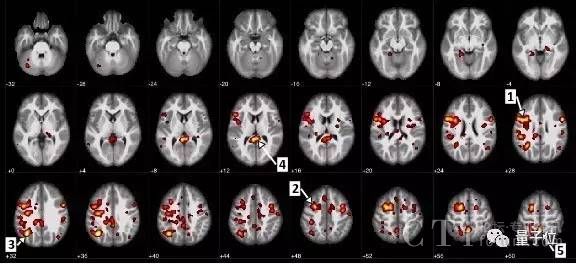

最近,IBM和阿尔伯塔大学联手进行了一项开创性的研究,使用简单的MRI(磁共振成像)扫描加一个神经网络,就能通过大脑的血流情况,来诊断神经分裂是否会发病,以及症状的严重程度。

这个研究团队,首先使用95份匿名fMRI(功能性磁共振成像)图片训练神经网络,这个数据集包括精神分裂患者和健康对照组。这些图片反映的是完成简单的音频联系后,脑内血液流动的情况。最后这个网络分辨患者和对照组的准确率达到74%。

“我们已经在大脑中发现许多异常连接,未来会进行进一步的探索研究”,阿尔伯塔大学教授Serdar Dursun说,AI创建的模型得以让研究人员更进一步。

这个模型还能预测症状的严重程度,而这可以用来制定更为有效的治疗方案。